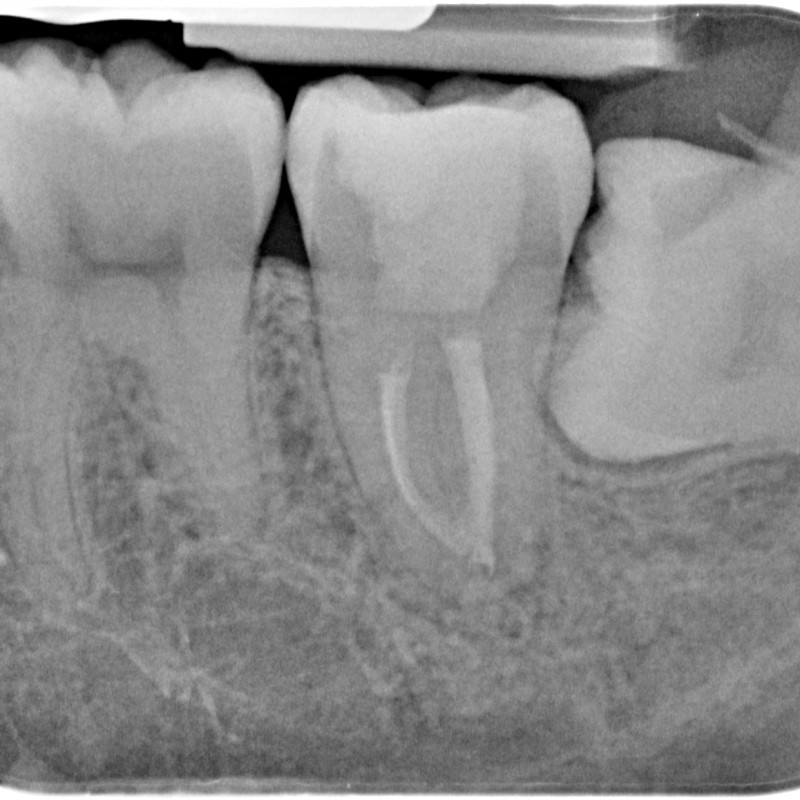

780613-05-5283-X-20150507-162045-XAFPNU2HWLK-4